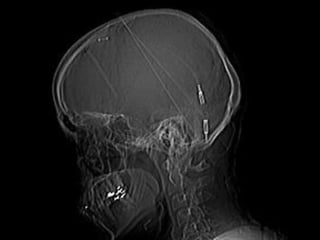

Retinite pigmentosa edRetinite pigmentosa ed

idrocefalo congenitoidrocefalo congenito

G.V. 41 aG.V. 41 a

Retinite pigmentosaRetinite pigmentosa

D.V. 41 aD.V. 41 a